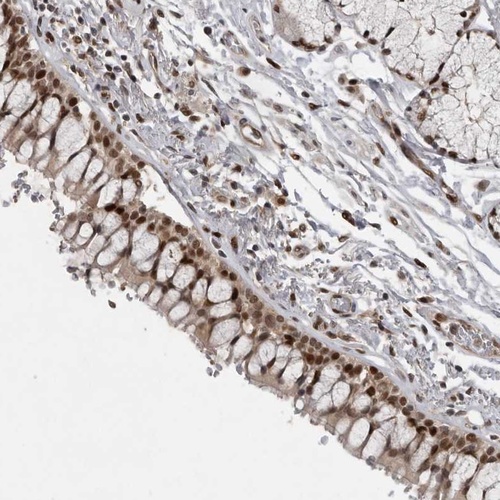

Immunohistochemical staining of human bronchus shows strong nuclear positivity in respiratory epithelial cells.